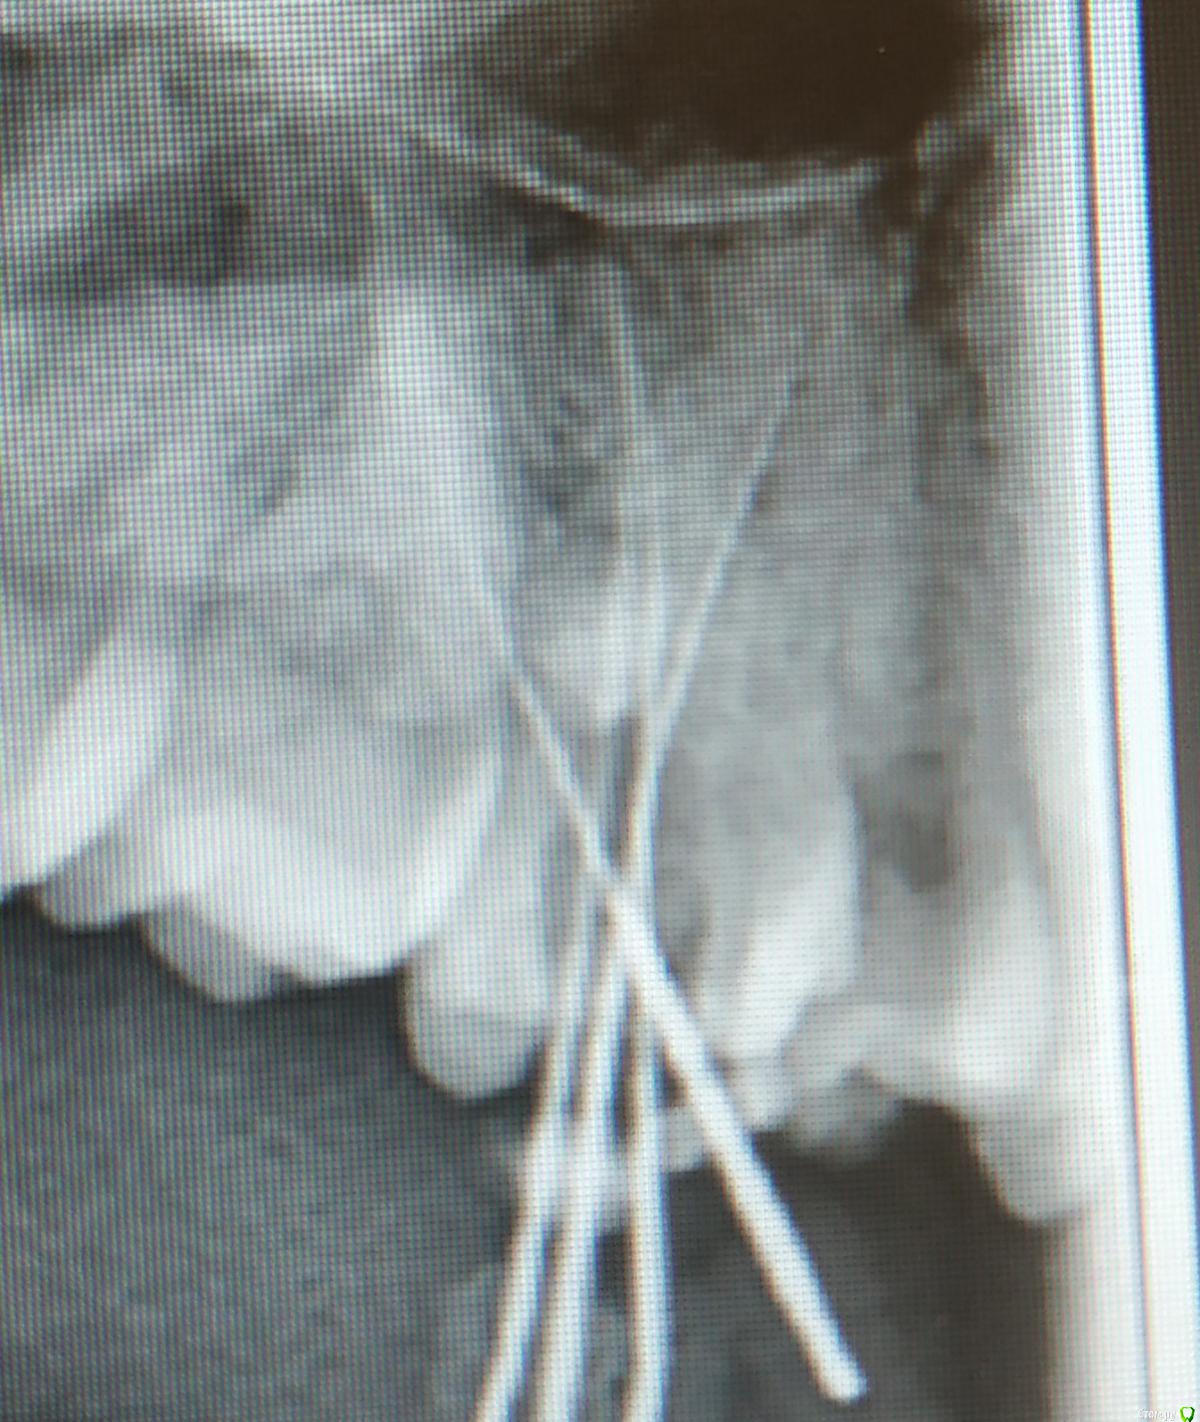

FVValerievna Опубликовано 14 сентября, 2019 Поделиться Опубликовано 14 сентября, 2019 Здравствуйте, подскажите пожалуйста, возможно ли, что пропущен канал? Ситуация такая: в полости рта четко видно 4 устья, на рентгене с инструментами тоже видно 4 канала, но на контрольном снимке не вижу 4й канал, хотя в полости рта запломбировано все 4 устья. Возможно ли такое наслоение? 1 Ссылка на комментарий

vse32 Опубликовано 14 сентября, 2019 Поделиться Опубликовано 14 сентября, 2019 Наслоение конечно возможно. Но на Вашем снимке после пломбировки видно, что каналов 4 штуки. Ссылка на комментарий